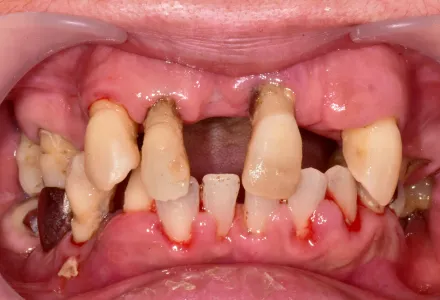

全顎治療症例2

Before

After

- 治療名

- インプラント治療+セラミックの詰め物

- 患者さん

- 70代 女性

- 執刀医

- 田中院長

- 治療

内容 - 今回はインプラント治療とセラミック詰め物を組み合わせて前歯の審美回復を行いました。歯と歯茎のラインまで自然に整えることで、機能面の改善に加えて美しい口元を実現しました。患者様から「仕上がりが非常に自然で、治療前に感じていたコンプレックスが解消されました」とのお声をいただきました。

- 治療期間

- 5ヶ月

- 治療費

- 4,500,000円〜

- リスク

- 外科処置を伴うため、術後の腫れ・痛み・内出血が生じることがあります。

また、強い力が加わると、セラミックが欠けたり割れたりする場合があります。